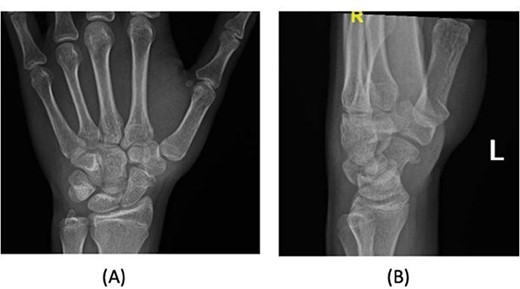

A 15-year-old boy, right handed, was not known to have any chronic medical illnesses. He presented to the emergency department (ED) with a history of severe left-wrist pain and swelling after falling from a height of 5–6 meters on an outstretched hand with the wrist in extension three hours prior to the ED presentation. The pain is mainly located in the left wrist’s dorsum and distal part of the forearm. Increasing pain with movement and relived with immobility. On examination, a normal-appearing wrist. No open wounds or lacerations, nor abrasions. There is no obvious deformity. There was mild swelling in the wrist. Tenderness over the dorsal radial wrist, including the anatomical snuff box. The range of motion was restricted due to pain. The neurovascular examination was normal. A plain radiograph in the ED showed a scaphoid tubercle fracture and a capital bone fracture. Initial radiographs are shown in Fig. 1). The patient was taken for computerized tomography (CT) to better define the extent of the injury (Fig. 2). A CT scan showed a displaced fracture of the capitate carpal bone, with an avulsion fracture at the distal tubercle of the scaphoid carpal bone, with extension to the articular surface. In addition to perilunate fracture, the rest of the carpal bone’s alignment is maintained. The patient was shifted to the operating room for open reduction and k-wire fixation of the scaphoid and capitate fracture of the left hand. Under general anesthesia, a tourniquet was applied. The incision was over the dorsal aspect of the left wrist, proceeding with the wrist capsule opening. The fracture was fixated with two Kirschner wires. Alignment was assured intraoperatively with an x-ray (Fig. 3). Plain radiographs post-fixation showed intact alignment. Postoperatively, the wrist was immobilized in a long-arm splint. The Kirschner wires and the protected splint were removed at 5 and 8 weeks, respectively. Immediately afterward, physiotherapy started. A few months following surgery, the site of the fracture healed radiologically. The patient had no pain, and the range of motion was acceptable after a period of physiotherapy. Figure 4 demonstrates a medical illustration of a scaphocapitate fracture.

Posteroanterior and oblique radiographs taken intraoperatively after fixation, demonstrating proper alignment of hardware.